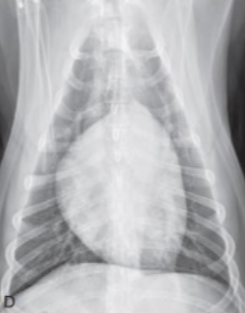

| Generalized cardiomegaly |

|---|

| RA, RV, LA, LV๊ฐ ๋ค ์ปค์ง โ Globoid heart |

| - Pericardial effusion - ์ฌํ ์์ชฝ ์ฌ์ฅ๋ณ (MVI + TVI) - PPDH (Peritoneopericardial diaphragmatic hernia) - Cardiomyopathy (DCM) - Anesthesia, bradycardia |

![]() |